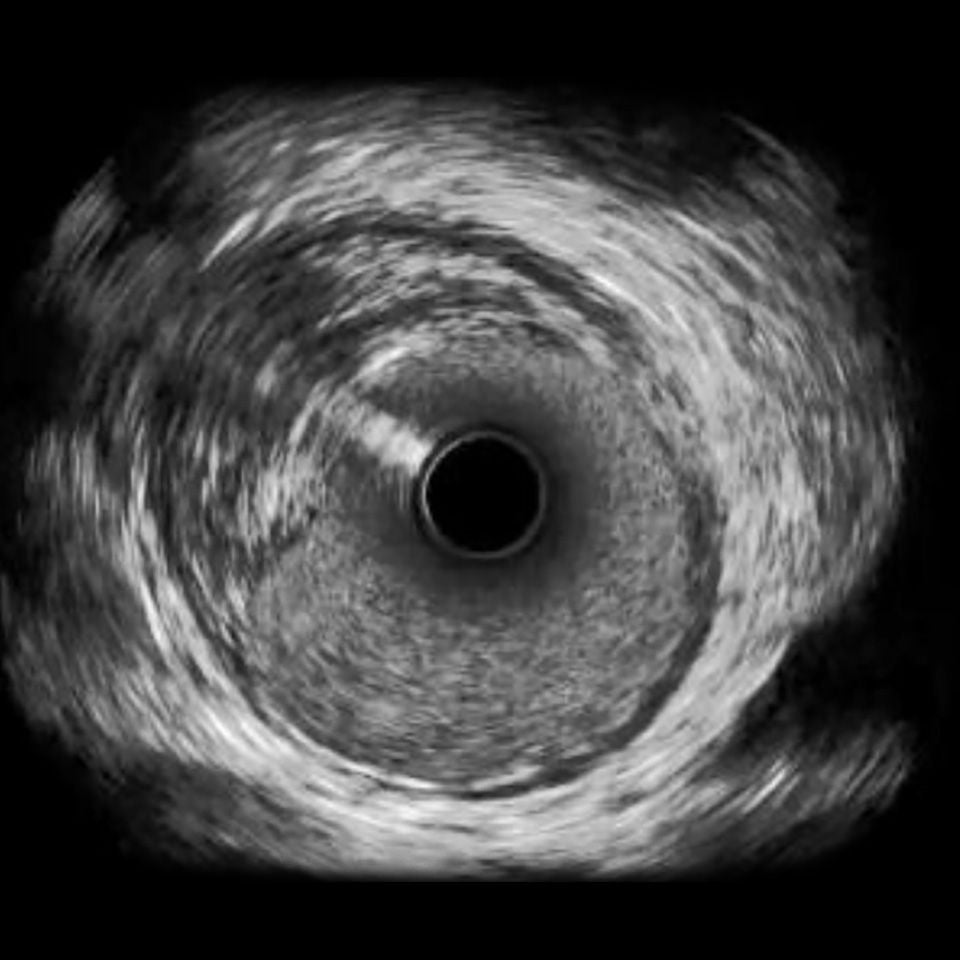

Philips Volcano Eagle Eye Platinum Imaging Catheter 20MHz

IVUS image of inside a coronary vessel using the 20MHz Philips Volcano Eagle Eye Platinum catheter

Axial resolution: <170 µm